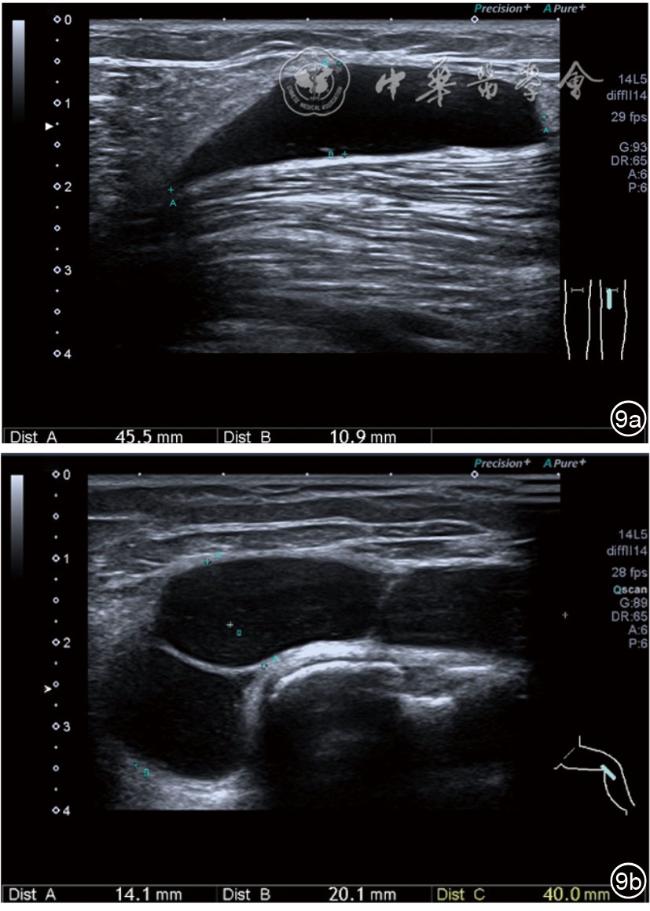

髂胫束是包绕大腿深筋膜——阔筋膜的外侧增厚部分,从髂嵴前缘的外侧缘起,分为上下两层,包裹阔筋膜张肌,并与之紧密结合不易分离,近端大转子水平源自阔筋膜张肌和臀大肌,向远端走行于股外侧肌浅方,途径股骨外侧髁,最终止于胫骨Gerdy结节、腓骨头和膝关节囊。在Gerdy结节处,髂胫束与股二头肌及股外侧肌纤维相互交织。髂胫束由致密组织构成,厚约1.9 mm。主要功能包括:(1)对膝盖的外部方面提供静态稳定性。(2)控制内收运动和大腿的减速作用。髂胫束起到固定膝关节,防止胫骨过度内旋,伸直膝关节和外展髋关节的作用。血液及营养供给较肌肉组织少。